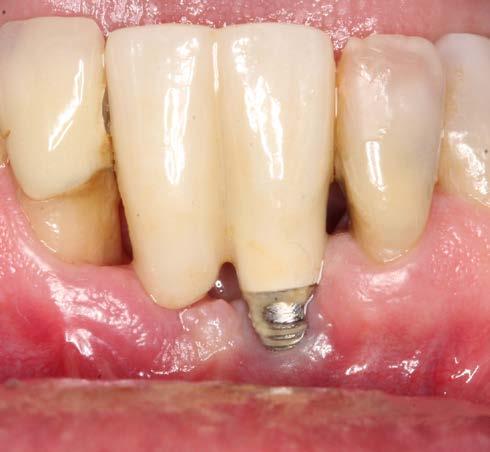

A 67-year-old gentleman was referred with the chief complaint of having discomfort in the area of implant supported bridge (31 and 41). The clinical and radiographic examination revealed presence of inflammation, lack of attached mucosa, as well as progressive bone loss since installment of the implant. The diagnosis of active periimplantitis #31 implant was made. Due to the patient's satisfactory plaque control and low levels of full mouth plaque score, a surgical management was indicated. This included a surgical debridement, partial implantoplasty in the exposed part, as well as soft tissue conditioning in order to increase the band of attached mucosa in the form of free gingival grafting. This treatment in combination with regular CIST (Implant Supportive Therapy) resulted in elimination of the inflammatory component (BOP and progressive bone loss) as well as facilitation of the self-performed plaque control via tissue graft.

2. The clinical view represents exposed threads, lack of attached mucosa, and patient discomfort.